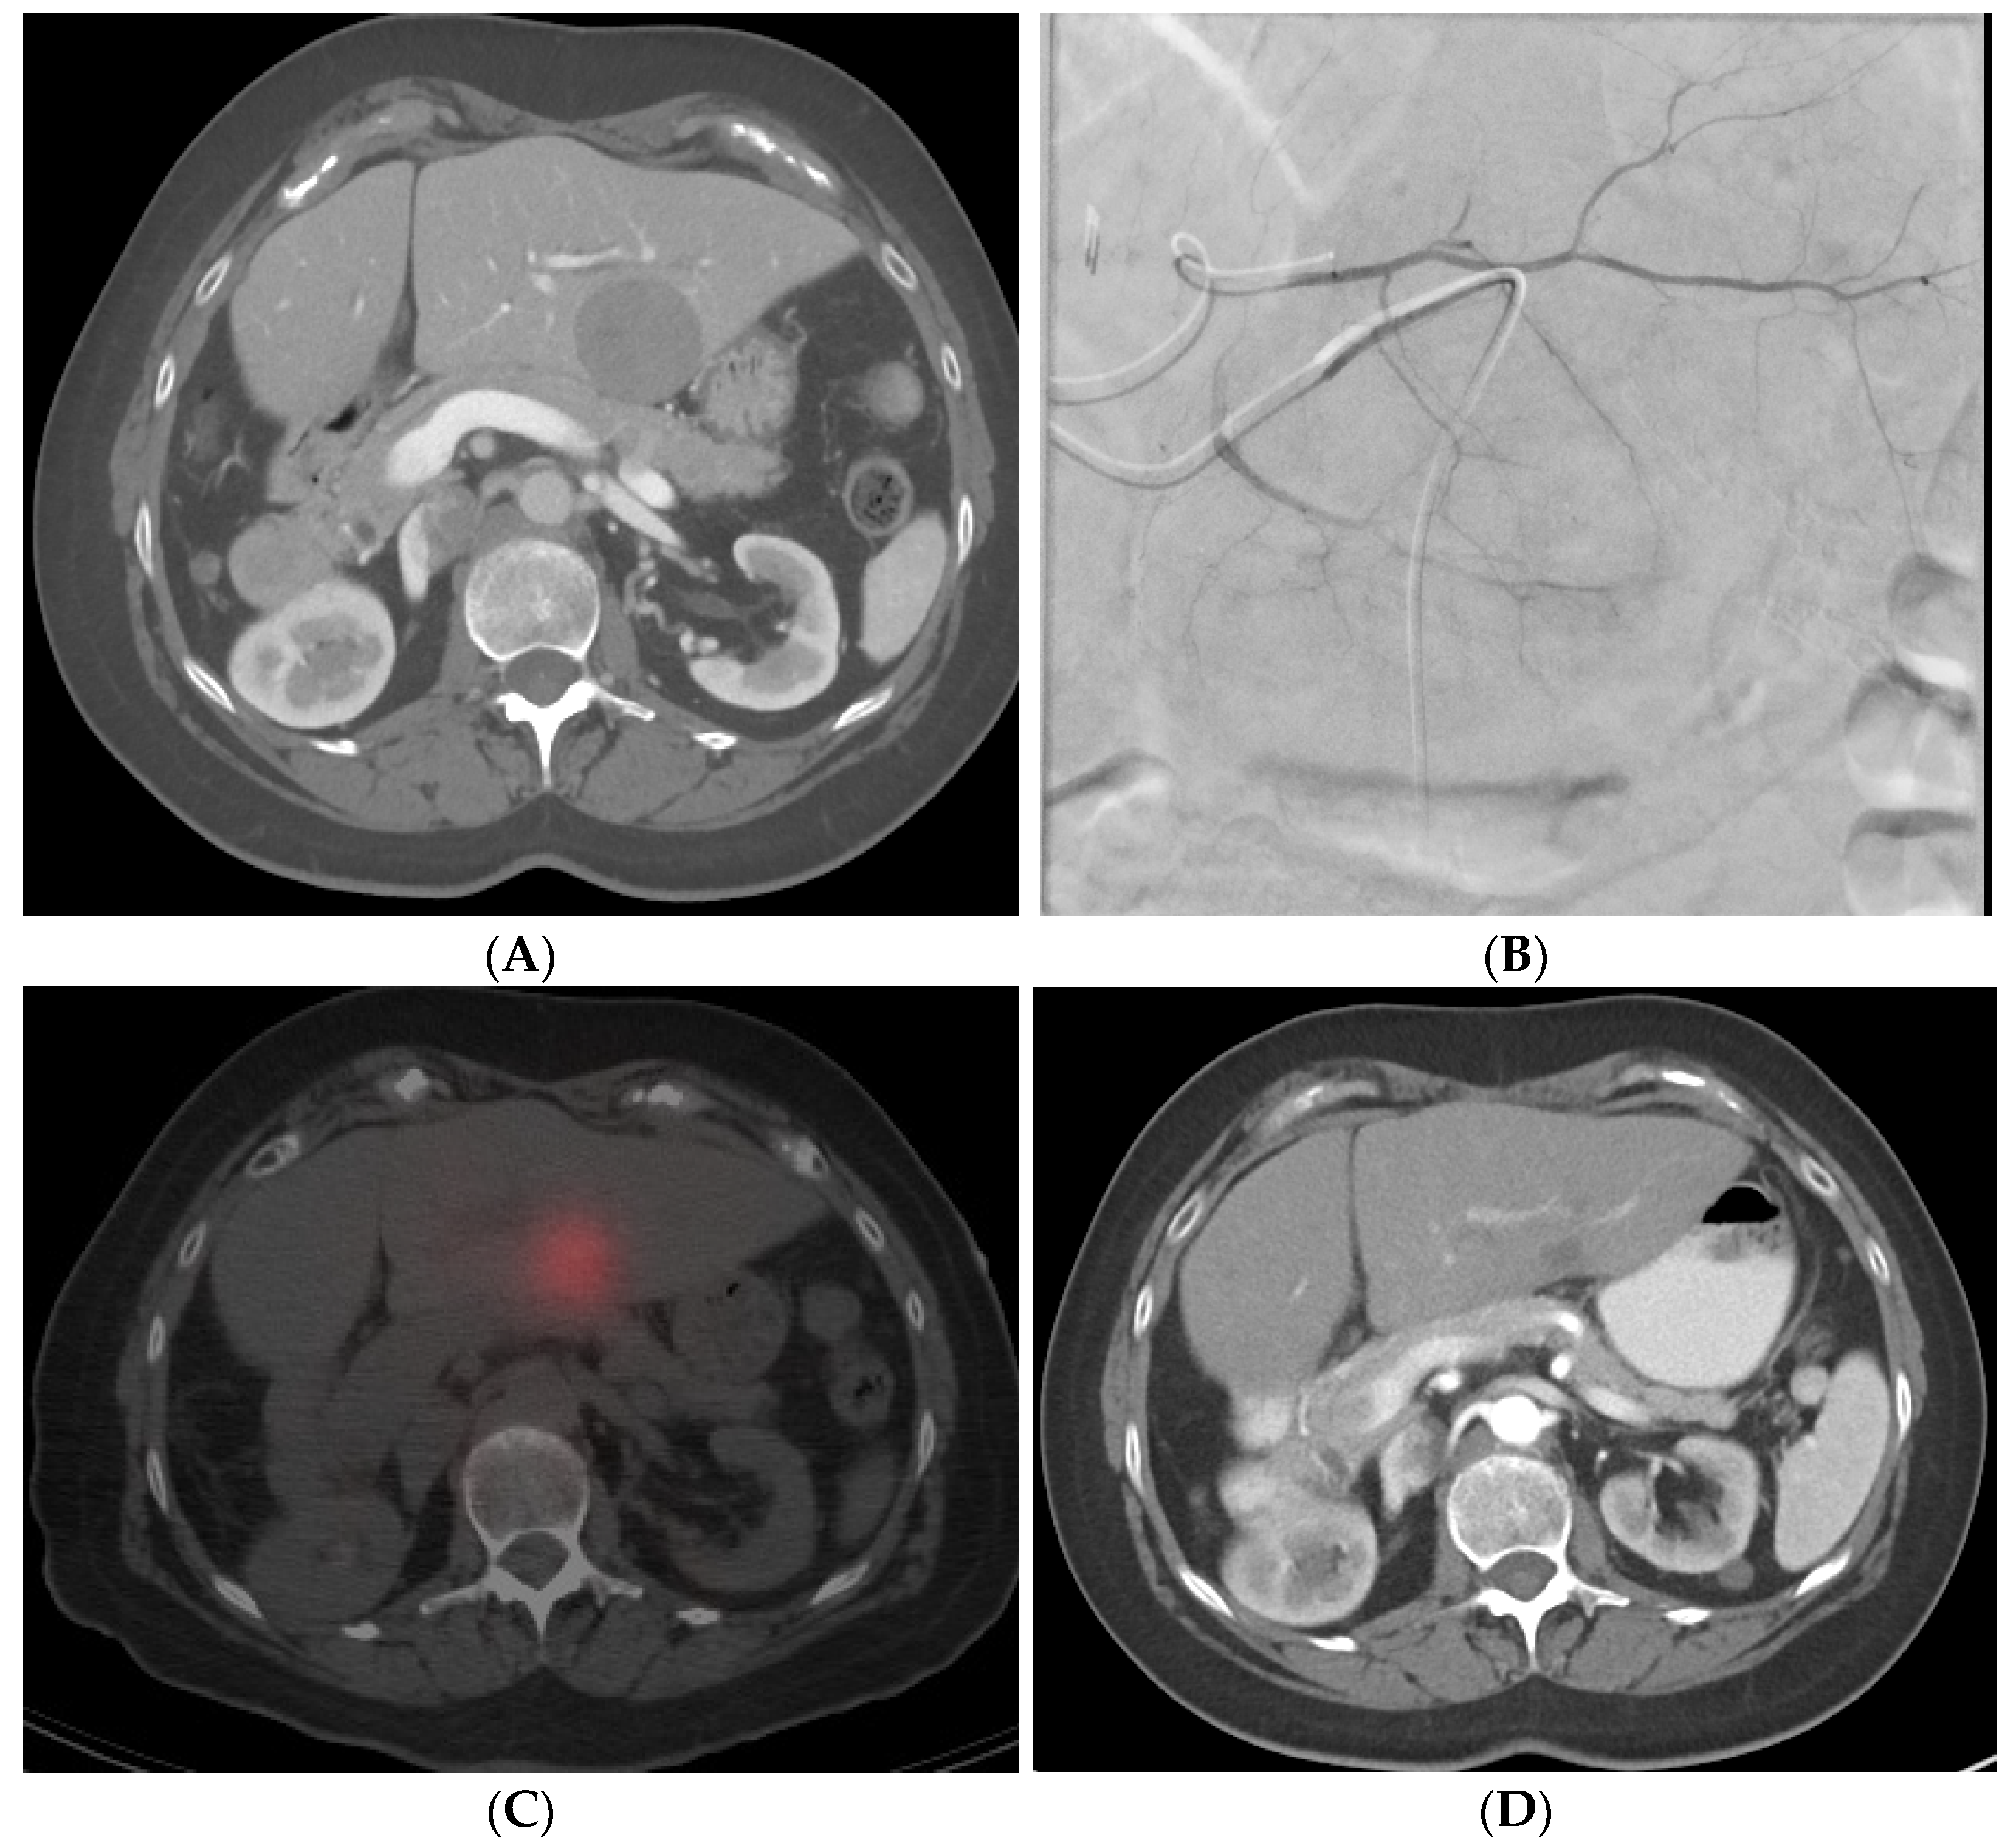

7.2.3. Selective Internal Radiation Therapy (SIRT)

8.4. Selective Internal Radiation Therapy (SIRT)

12.1. Imaging Response Criteria

- Gabr, A.; Riaz, A.; Johnson, G.E.; Kim, E.; Padia, S.; Lewandowski, R.J.; Salem, R. Correlation of Y90-Absorbed Radiation Dose to Pathological Necrosis in Hepatocellular Carcinoma: Confirmatory Multicenter Analysis in 45 Explants. Eur. J. Nucl. Med. Mol. Imaging 2021, 48, 580–583. [Google Scholar] [CrossRef] [PubMed]

- Cheng, B.; Sethi, I.; Villalobos, A.; Wagstaff, W.; Schuster, D.M.; Bercu, Z.; Brandon, D.; Kokabi, N. Determination of Tumour Dose Response Threshold and Implication on Survival in Patients with HCC Treated with Y90 Radiation Segmentectomy: A Simple Semi-Quantitative Analysis. Nucl. Med. Commun. 2021; Publish Ahead of Print. [Google Scholar] [CrossRef] [PubMed]